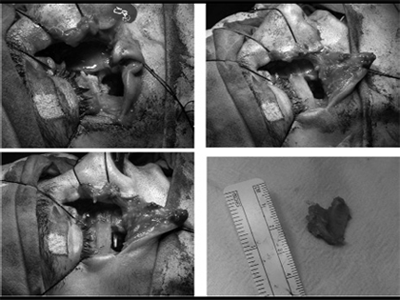

23.09.09 под общим обезболиванием произве-дена рефрактура неправильно сросшихся костных фрагментов, контурная пластика подглазничной области справа, ревизия гайморовой пазухи с пластикой передней стенки ВЧП. Произведен разрез мягких тканей, начиная с нижнего наружного края глазницы до носовой кости справа, далее, меняя направление разреза вниз, до наружного носового прохода справа (рис. 3.1). Ткани рассекали послойно до кости с помощью распатора, обнажали нижний край глазницы и переднюю стенку ВЧП (рис.3.2).

Обнаружили неправильно сросшиеся костные от-ломки, которые освободили от мягких тканей (рис.3.3), вскрыли переднюю стенку ВЧП (гис.3.4), произвели ревизию ВЧП, удалили инородные тела и патологические грануляционные ткани. Полость ВЧП промыли антисептическими растворами, соз-дали соустье между ВЧП и нижним носовым ходом. Произвели репозицию и фиксацию костных отломков костным швом (рис.3.5), нижний край глазницы восстановили АДКМ (рис.3.6), произвели тампонаду ВЧП. Дефект передней стенки ВЧП восстановили фрагментом кости передней стенки ВЧП (рис.3.7), который фиксировали на мембрану из пчелиного воска (рис.3.8). Костный фрагмент с пчелиным воском укладывали на дефект передней стенки ВЧП (рис.3.9). Мягкие ткани подглазничной области укладывали на свои места и прошивали узловыми швами полиамидной нитью 5,0, которые удаляли на 8-е сутки после операции (рис. 3.10).

Рис. 3. Этапы контурной пластики подглазничной области, ревизии правой гайморовой пазухи с пластикой передней стенки ВЧП.

1.линия разреза; 2. нижний край глазницы и передняя стенка ВЧП; 3. освобождение неправильно сросшихся костных фрагментов передней стенки ВЧП; 4. вскрытие передней стенки ВЧП; 5. репозиция и фиксация костных отломков костным швом; 6. восстановление нижнего края глазницы АДКМ-ом; 7. создание соустья между ВЧП и нижним носовым ходом; 8. костный фрагмент передней стенки ВЧП; 9. мембрана из пчелиного воска с костным фрагментом ВЧП; 10. тампонада ВЧП; 11. закрытие дефекта передней стенки ВЧП мембраной из пчелиного воска с костным фрагментом ВЧП; 12. мягкие ткани подглазничной области, уложенные на свое место и прошитые узловыми швами.